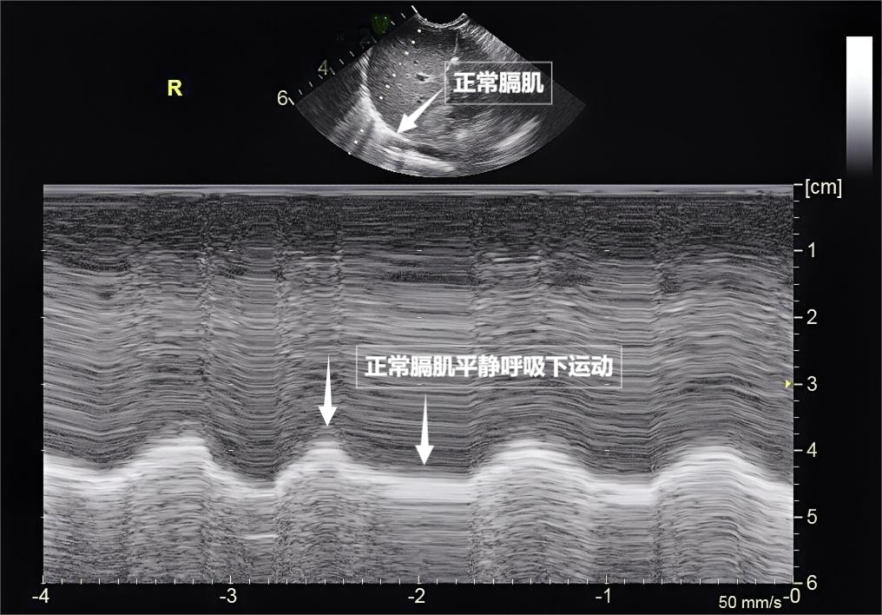

第三景:“呼吸的动力泵”的协同作战——呼吸肌肉呼吸看似简单,实则是多组肌肉精密配合的“团体操”。肺部超声不仅能观察肺的形态,更能通过实时动态影像,“捕捉”这些呼吸肌的活动状态,为评估呼吸功能提供独特视角。膈肌是呼吸肌的“总指挥”,位于胸腔与腹腔之间。平静呼吸时,膈肌收缩下沉,胸腔容积扩大,空气自然吸入;舒张时,膈肌回升,肺部弹性回缩完成呼气。超声下可见膈肌呈光滑弧形,随呼吸规律上下移动(见下图)。肋间外肌则是“肋间隙的升降机”,收缩时上提肋骨,扩大胸腔前后径,辅助吸气。这对“黄金搭档”承担了日常呼吸70%以上的工作量,是维持呼吸的“主力军”。

图为正常膈肌超声表现